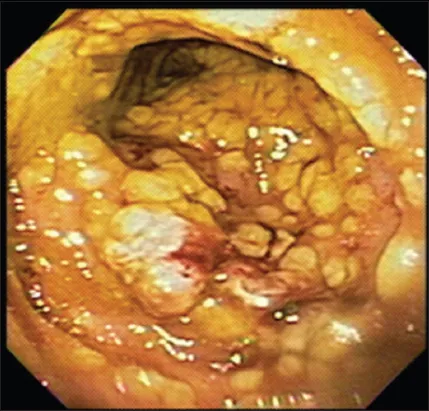

⭐ The toxins' destruction of the colonic epithelium leads to the formation of characteristic pseudomembranes-yellow-white plaques composed of fibrin, mucus, and inflammatory cells.

- Pseudomembranous colitis (yellowish-white plaques on colonoscopy)

- Clinical presentation ranges from mild diarrhea to life-threatening pseudomembranous colitis and toxic megacolon.